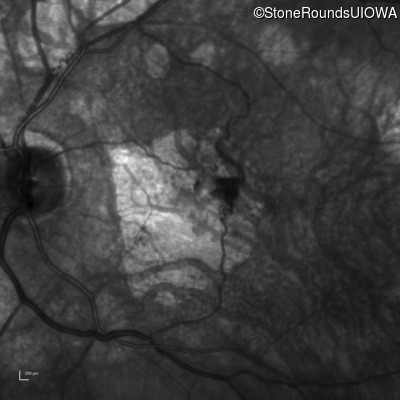

Infrared Fundus Photograph - Left - 20/100

Exemplar